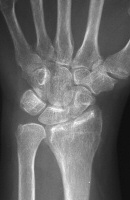

| This patient presented with

persistent wrist pain, swelling and stiffness one year out from closed

reduction and external fixation of a n intraarticular distal radius

fracture. |

| No prior films were

available. Plain films suggested a depressed section of the radial edge

of the lunate fossa and loss of dorsal tilt. |